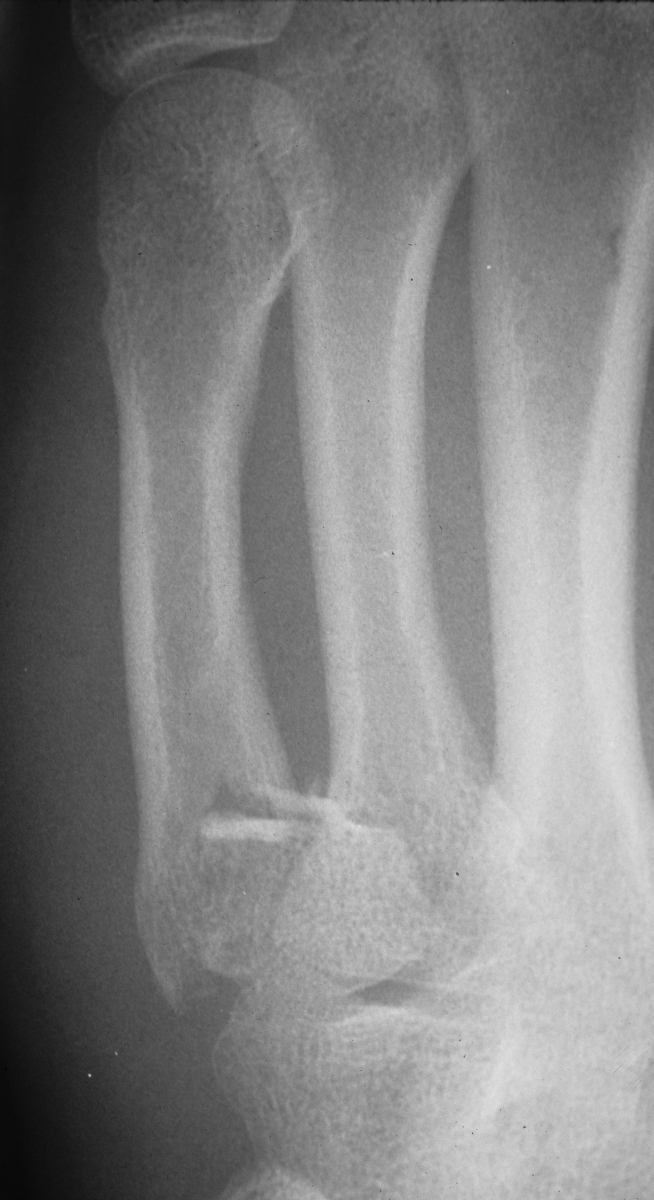

Rotated unstable spiral oblique proximal phalanx

fracture. |

| Reduction and fixation. |

| Appearance at four

weeks. |

| Late result. |